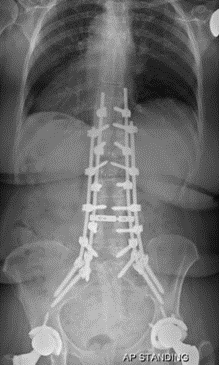

图12 CBT+TT+多棒固定

CBT+TT+多棒固定

从融合节段向活动节段未行过渡性手术,导致局部应力分布不均,局部应力过于集中,也是交界性问题的危险因素之一。

长节段固定时,融合区和活动区应适当行过渡性手术,可降低PJK发生的风险。

图13 长节段全椎弓根螺钉固定,局部应力过于集中